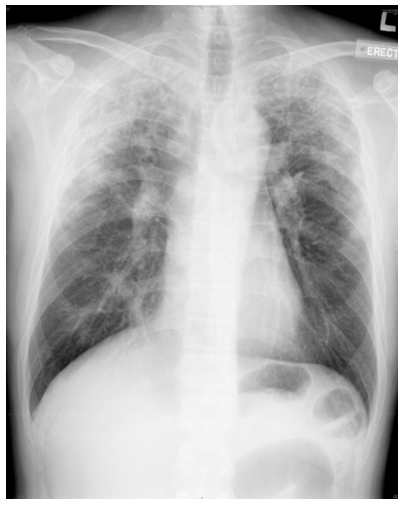

Fig. 1 CXR upon presentation

His chest x-ray (CXR) showed bilateral upper lobe infiltrates with peripheral predominance (figure 1). Erythrocyte sedimentary rate (ESR) was elevated at 120mm/hr. Leukocytosis was noted with total white cell count at 18.0×10^9/L. Reversed A/G ratio was noted (albumin 30g/L, globulin 56g/L). Although two sputum samples for acid-fast bacilli (AFB) smear were negative, he was empirically treated as pulmonary tuberculosis (TB) with isoniazid, rifampicin, pyrazinamide and ethambutol with the clinical presentation and was subsequently referred to the chest clinic for subsequent management.